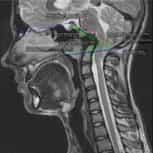

你有Chiari畸形第一型、 脊髓空洞症或是脊柱側彎嗎?

填寫免費終絲疾病遠距咨詢:Chiari畸形第一型、原發性脊髓空洞症、原發性脊柱側彎、顱底凹陷、扁平顱底、齒狀突畸形、腦幹扭結症